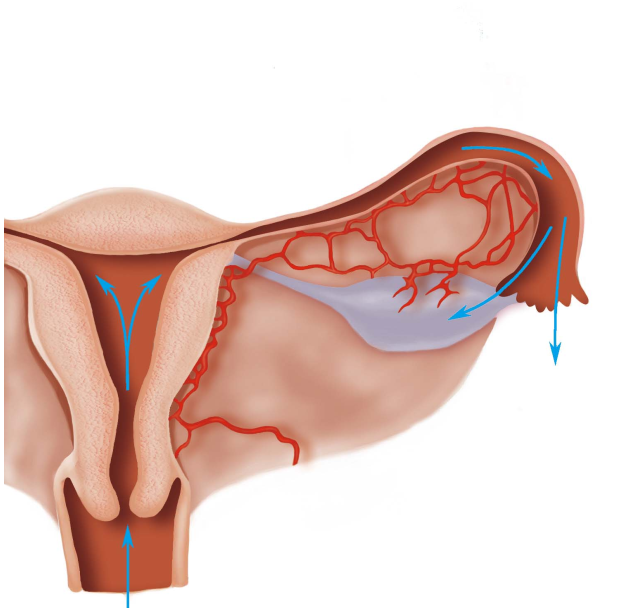

1.沿生殖道黏膜上行蔓延 病原体侵入外阴、阴道后,或阴道内的病原体沿宫颈黏膜、子宫内膜、输卵管黏膜,蔓延至卵巢及腹腔,是非妊娠期、非产褥期盆腔炎性疾病的主要感染途径。淋病奈瑟菌、沙眼衣原体及葡萄球菌等,常沿此途径扩散。(图20-1)

图20-1 炎症经黏膜上行蔓延